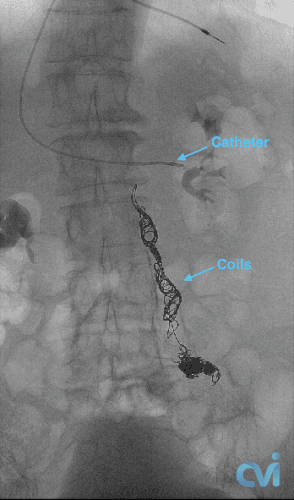

During this procedure, our image-guided specialist will numb the skin and insert a catheter (a tiny tube) into a vein in the neck or groin. The placement is done with precision using ultrasound guidance minimizing pain.

Using x-ray guidance a smaller catheter is then guided into the abnormal ovarian or pelvic veins. The abnormal vein is then treated by placing tiny coils and a specialized fluid causing the vein to seal down. This then restores normal blood flow in the body and improves related symptoms.